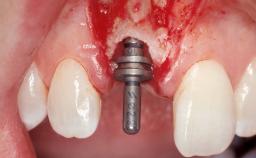

A 30-year-old female patient had lost tooth 21 and was referred to our clinic for consultation and treatment. Due to advanced apical infection, tooth 21 had been extracted two months earlier at another clinic and an acrylic-resin tooth had been bonded to the adjacent teeth. The patient desired implant treatment to avoid any damage to the adjacent natural teeth. While the patient had no history of any systemic disorder, she was a heavy smoker and exhibited medium to advanced periodontitis in the entire jaw. After the initial treatment to achieve a pocket probing depth of less than 4 mm and no bleeding on probing, a decrease in the height of the papillae mesial and distal to the extraction site and overall gingival recession were observed.

Type of Implants One-Piece|Reduced-Diameter

Bone Augmentation Horizontal|Staged

Augmentation Materials Autogenous chips|Membrane

Soft Tissue Grafting Simultaneous

Bone Volume Deficient horizontally, requiring prior grafting